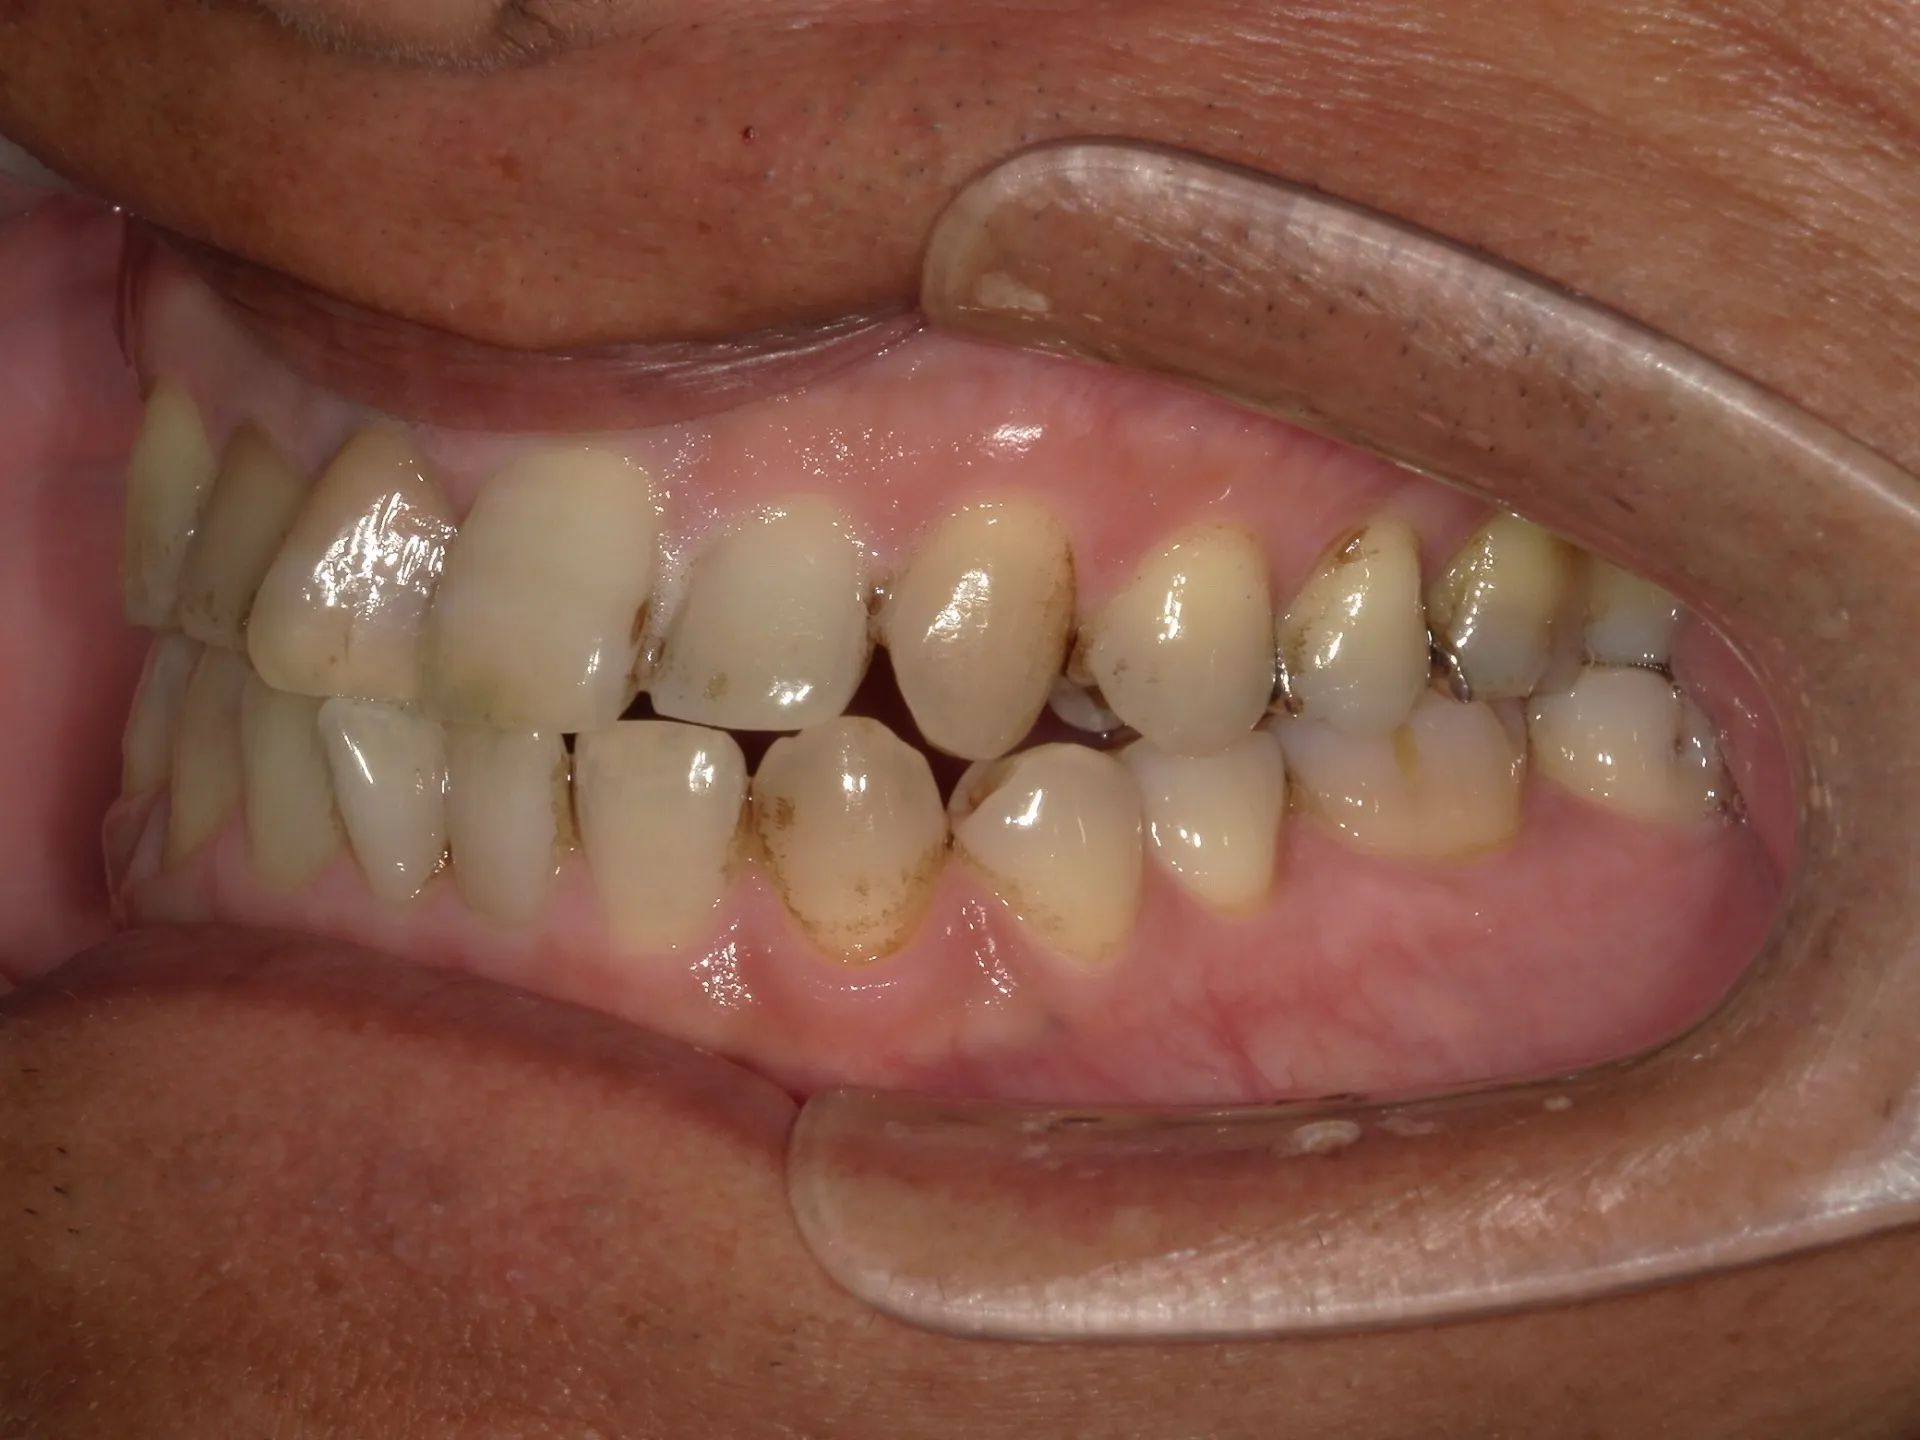

目的:予防、見た目の改善、仕上げ磨き

対象:歯石があるなしに関係なく、バイオフィルムやステインを徹底的に除去

範囲:歯科医療の保険枠を超えたケア(ホワイトニングほどではないが審美寄り)

内容:

専用のラバーカップやブラシ、ペーストで歯面を研磨

細かい着色やザラつきの除去

エアフローと呼ばれる清掃用の粉を吹き付けて着色を除去

仕上げにフッ素塗布を行う場合も多い